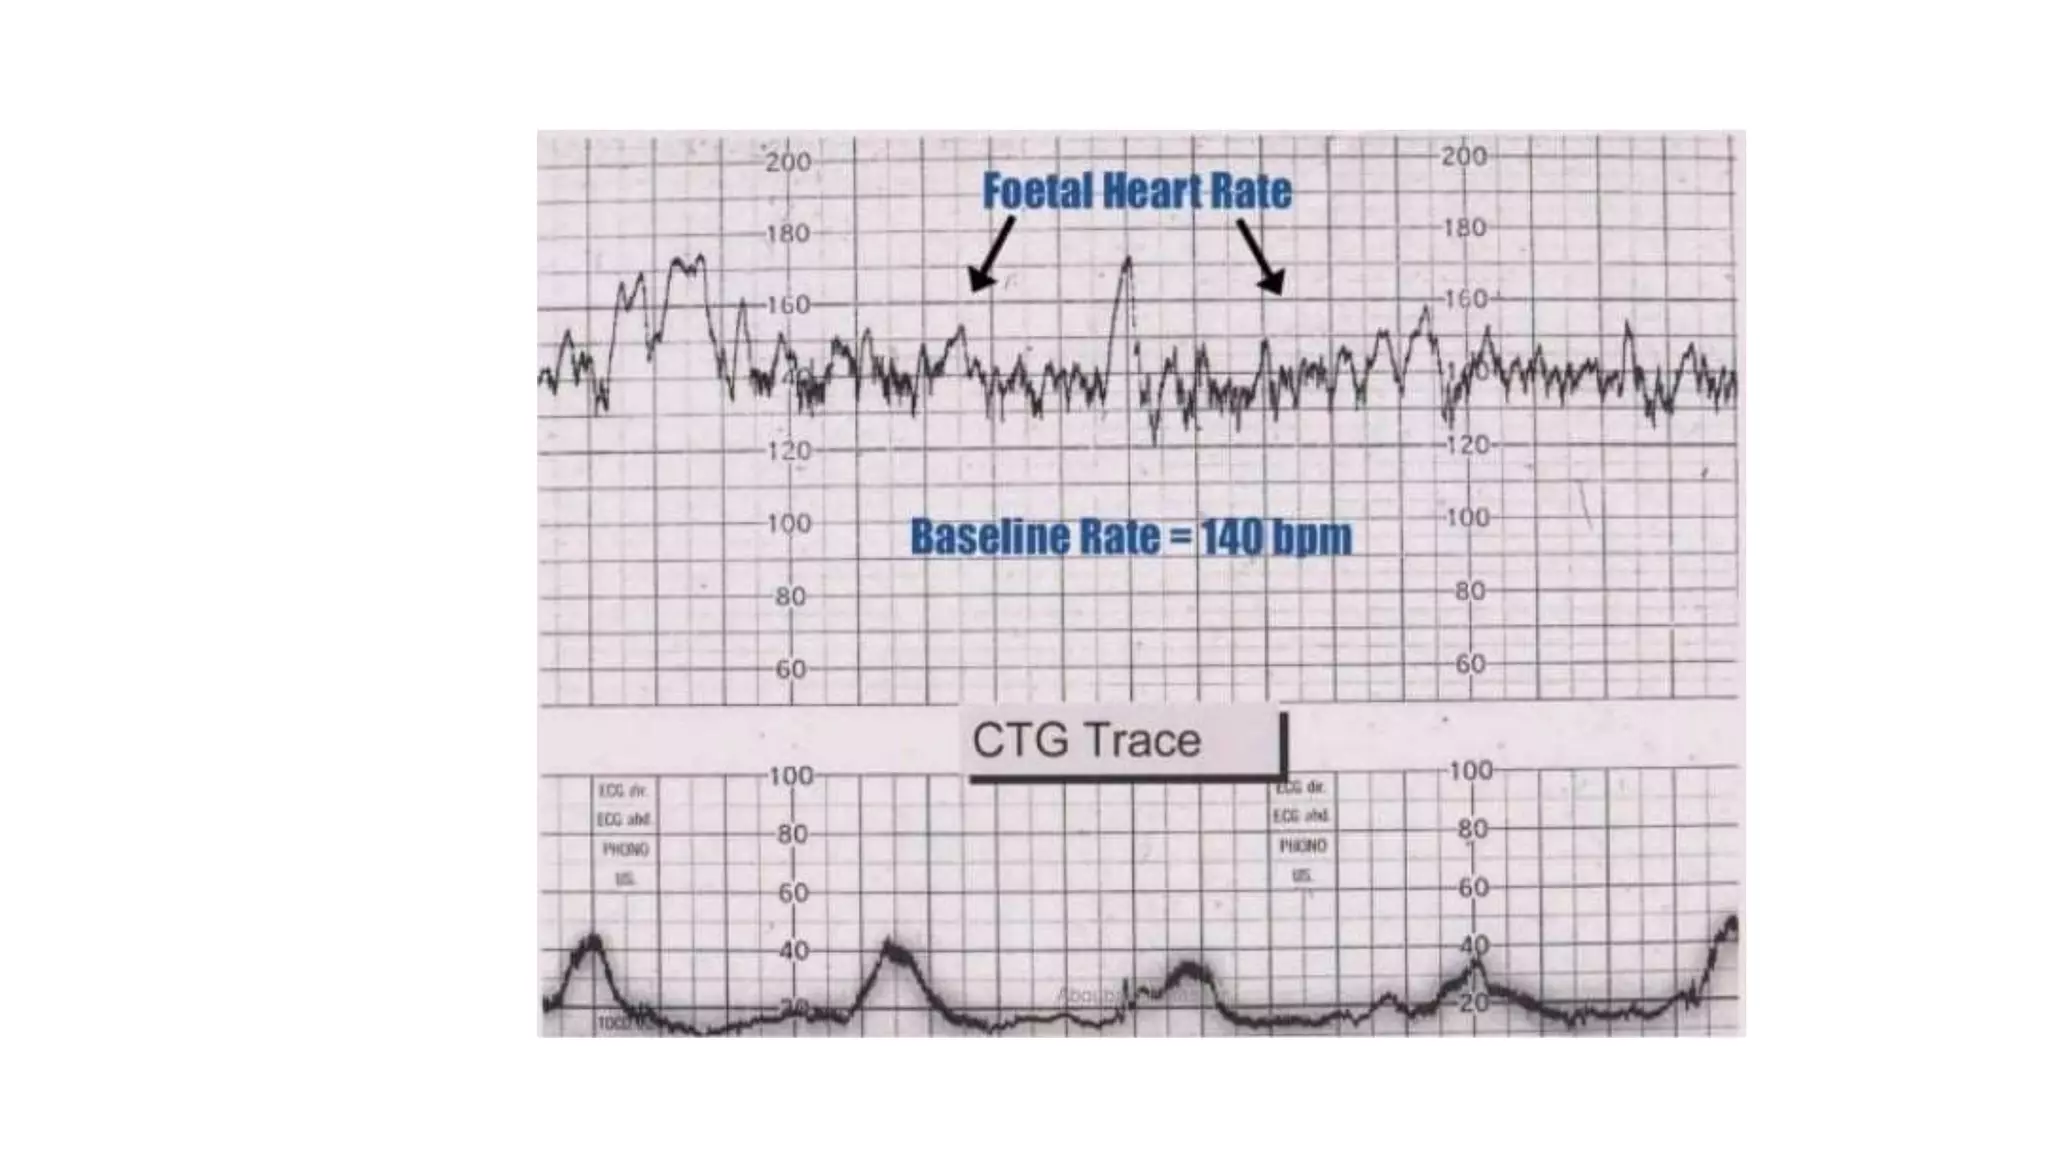

The document discusses key metrics for monitoring a baby's heart rate in utero, including the normal baseline rate of 100-160 bpm and variability. It also covers types of accelerations and decelerations that can occur, such as early or late, as well as bradycardia, which is an abnormally slow heart rate.